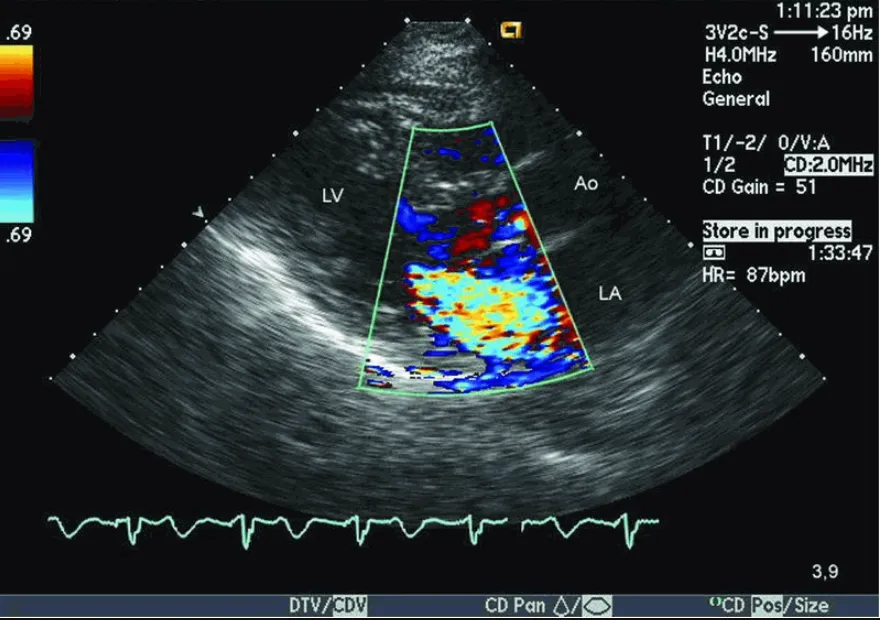

• Siêu âm tim: Siêu âm tim là một xét nghiệm quan trọng để chẩn đoán kênh nhĩ thất toàn phần. Nó có thể cho thấy các bất thường về cấu trúc của tim, bao gồm khuyết gối nội mạc (một dấu hiệu đặc trưng của kênh nhĩ thất), thông liên nhĩ và/hoặc thông liên thất, hở van hai lá và/hoặc van ba lá (do chẻ lá van hoặc thiếu mô van), tăng áp phổi (nếu có), giãn các buồng tim và giảm chức năng co bóp của cơ tim.